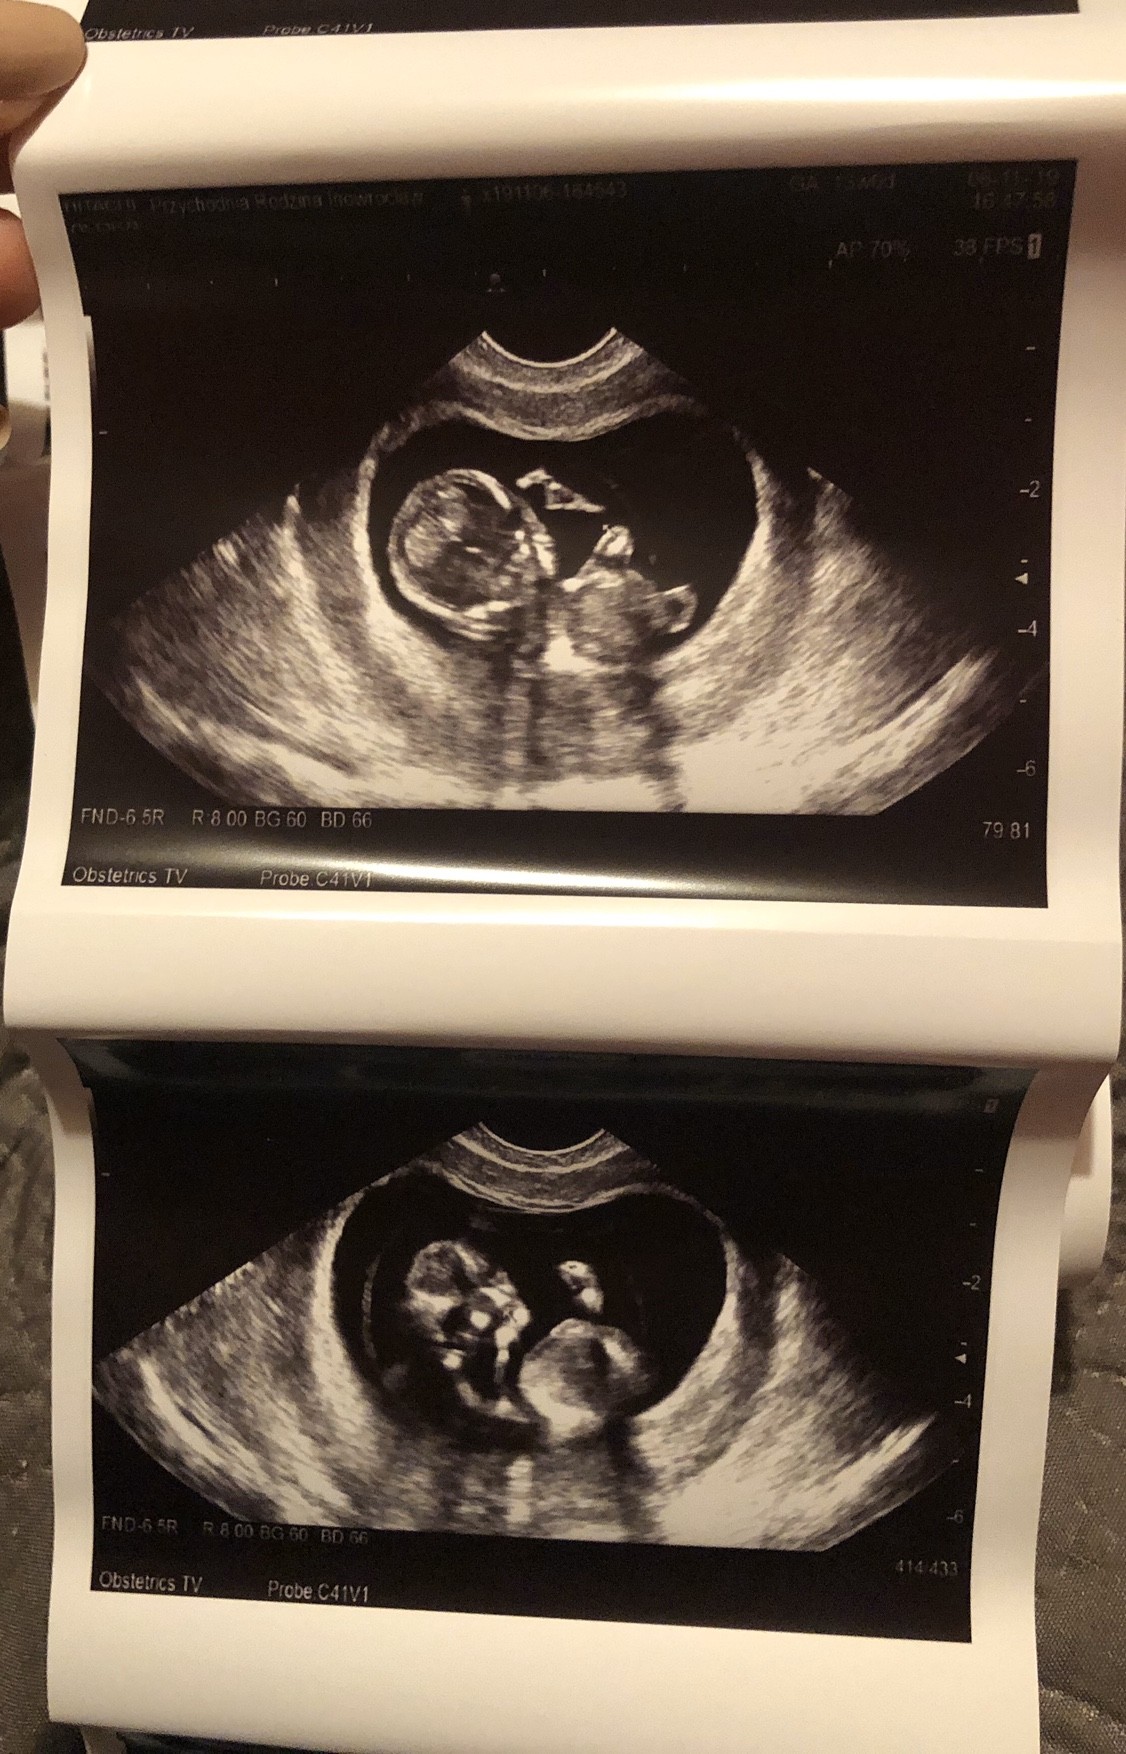

11+4

Na usg wiercił się niesamowicie, chyba zabiera mi całą energię bo ja chodzę półprzytomna ! No ale nie mam mu tego za złe ;) ;)